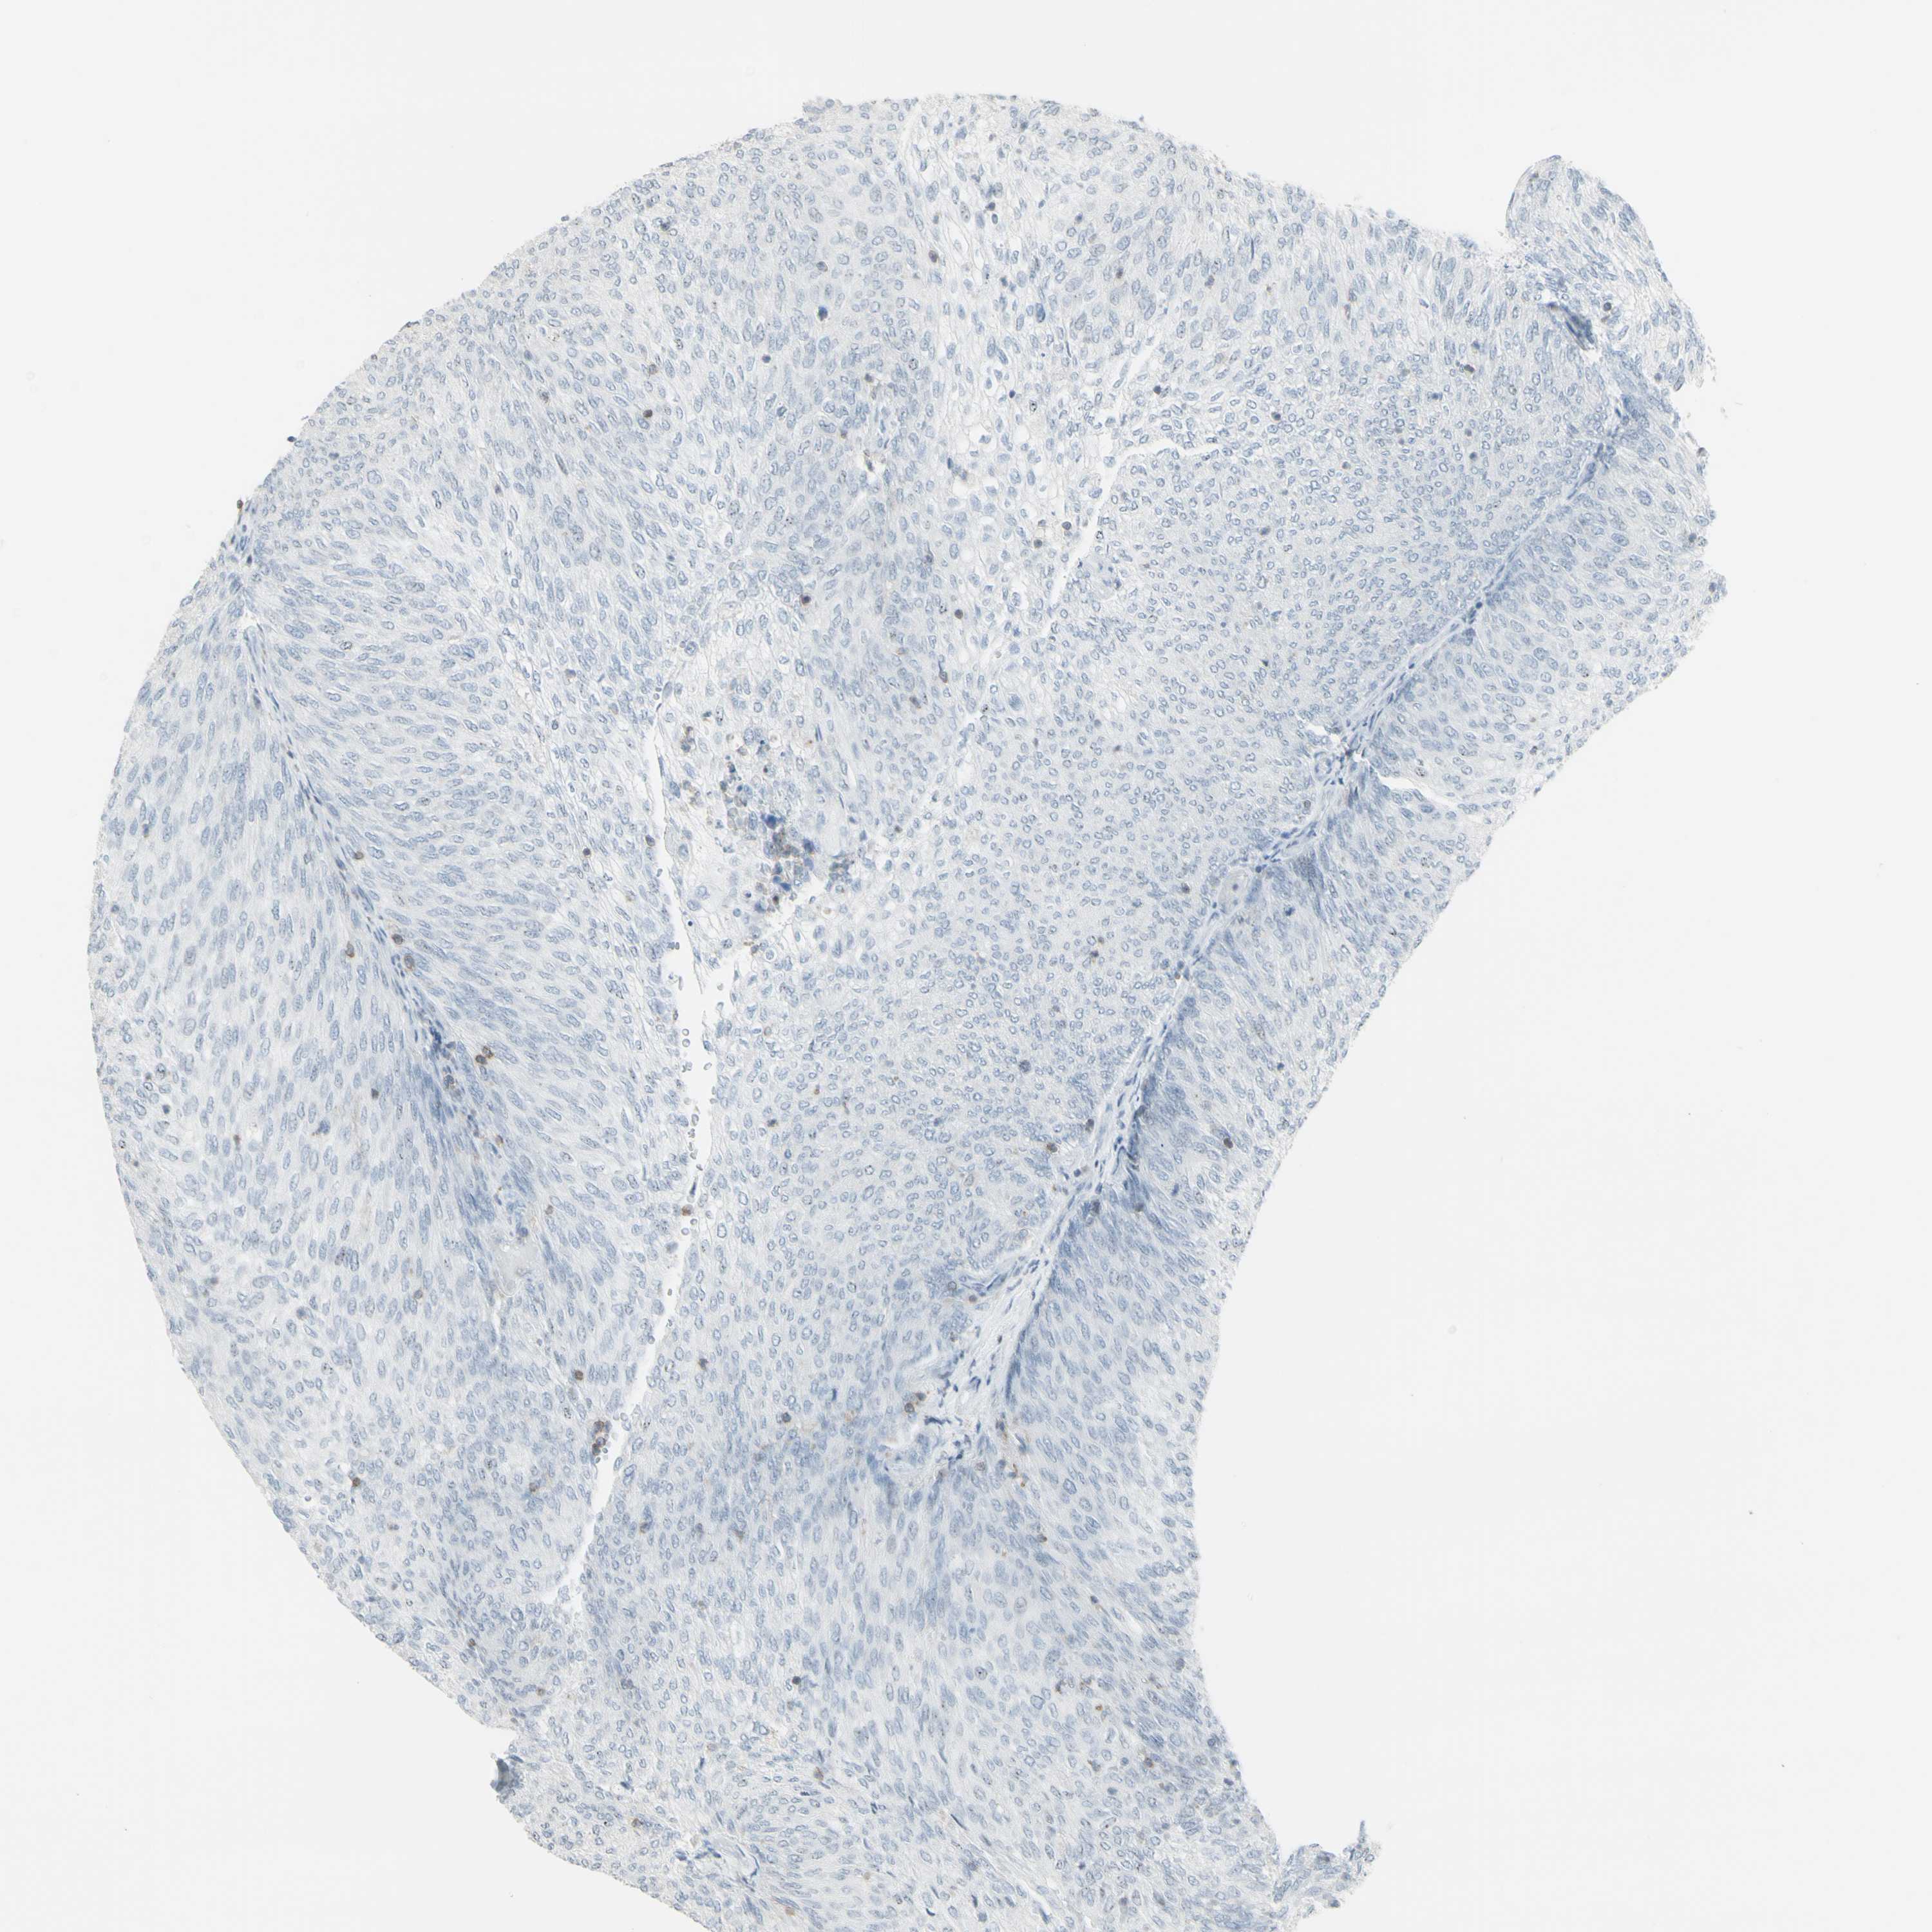

UROTHELIAL CANCER - Protein expressioni

A mouse-over function shows sample information and annotation data. Click on an image to view it in a full screen mode. Samples can be filtered based on level of antibody staining by selecting one or several of the following categories: high, medium, low and not detected. The assay and annotation is described here.

Antibody stainingi

Antibody staining in the annotated cell types in the current human tissue is reported as not detected, low, medium, or high, based on conventional immunohistochemistry profiling in selected tissues. This score is based on the combination of the staining intensity and fraction of stained cells.

Each image is clickable and will lead to virtual microscopy that enables deeper exploration of all samples and also displays staining intensity scores, fraction scores and subcellular localization as well as patient and tissue information for each sample.

Antibody HPA010964

Staining

High

Medium

Low

Not detected

Intensity

Strong

Moderate

Weak

Negative

Quantity

>75%

75%-25%

<25%

None

Location

Nuclear

Cytoplasmic/membranous

Cytoplasmic/membranous,nuclear

Urothelial carcinoma, Low grade

Urothelial carcinoma, High grade